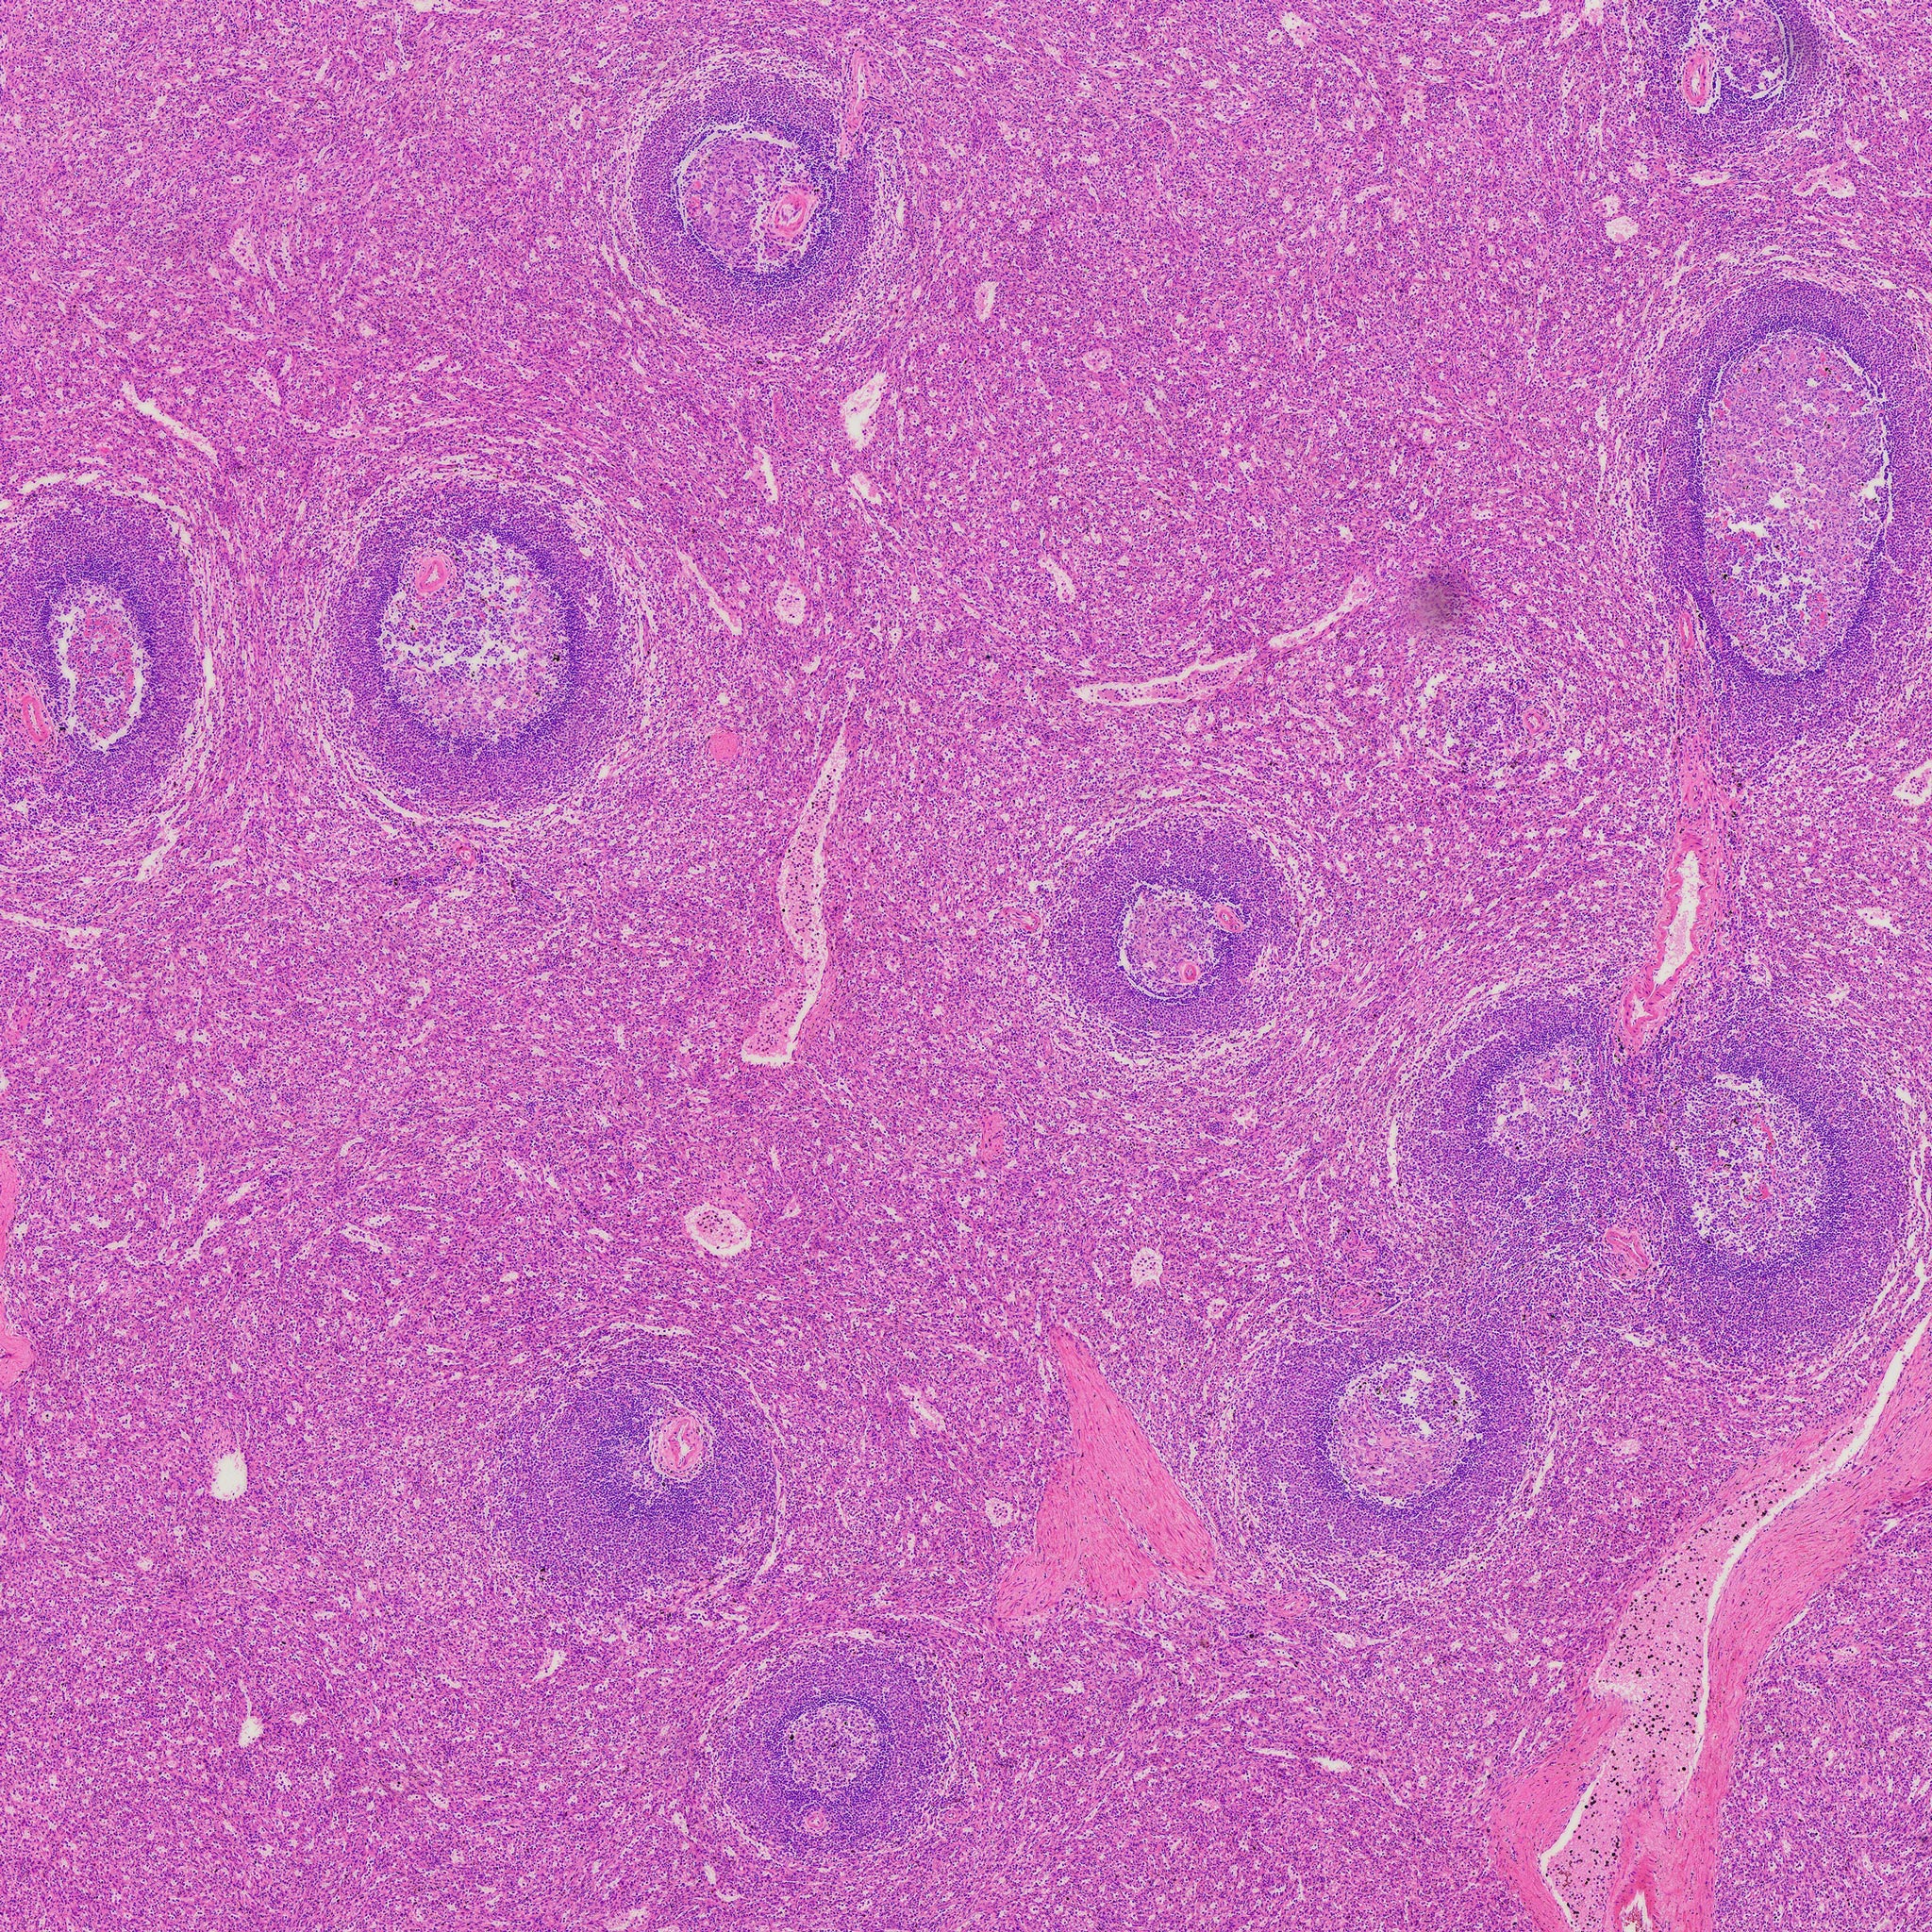

Thickness: 7-micrometer section

Stain: hematoxylin and eosin

Description of the Human spleen section:

- Thickness: 7-micrometer section

- Stain: hematoxylin and eosin

- Show: red pulp, splenic nodule, central artery